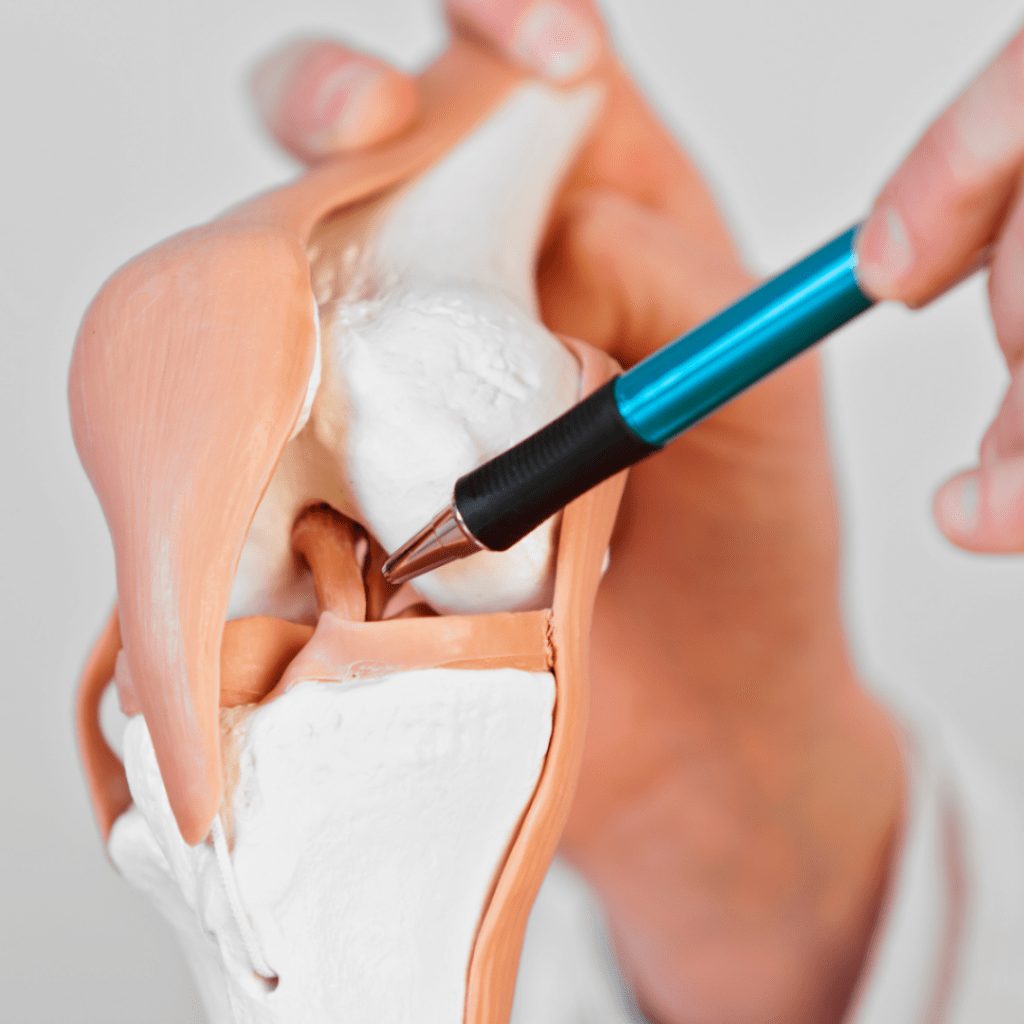

Gonatroz, diz eklemindeki kıkırdakların bozulması ve dejenerasyonu nedeniyle ortaya çıkan bir sağlık sorunudur. Gonatroz, diz ağrısı, sertlik, şişlik ve hareket kısıtlılığı gibi semptomlara neden olabilir. Genellikle yaşlı yetişkinlerde daha yaygın olmasına rağmen, her yaştan insanı etkileyebilir.

Diz Artroskopisi

Spor yaralanmaları spor veya egzersiz sırasında meydana gelen vücut hasarlarıdır. Bu yaralanmalar profesyonel sporcuların yanı sıra hafta sonu sporcuları ve egzersiz yapan bireylerde de yaygındır. Spor yaralanmaları kasları, kemikleri, eklemleri veya yumuşak dokuları etkileyebilir.